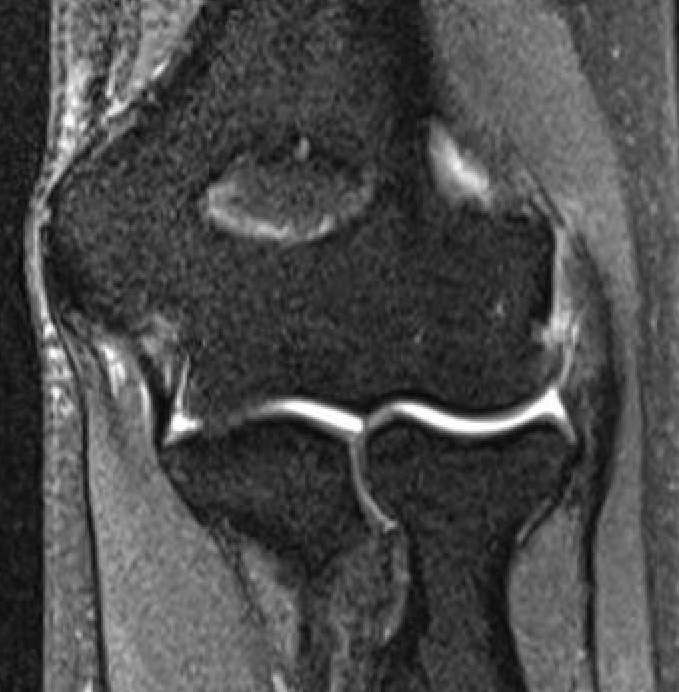

MRI

High grade partial tears of ECRB on lateral eipcondyle

Tendonopathy of the common extensor origin, with thickening and high grade tear partial tear